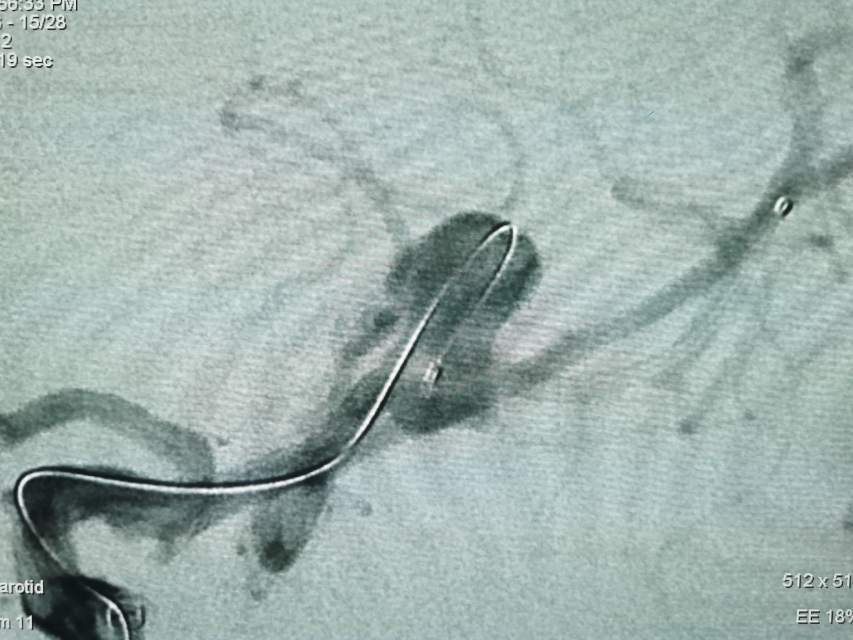

福建中年女性,近期在外查出“颅内动脉瘤”,经推荐转来我院诊治。患者的颈内动脉通路迂曲,动脉瘤也位置奇特,解剖复杂,动脉瘤远近段的血管弯弯绕绕,重重叠叠,眼花缭乱,难以兼顾找到最佳位置。最终克服困难,将“基底型”动脉瘤改变为“侧壁型”动脉瘤,顺利给予治疗……